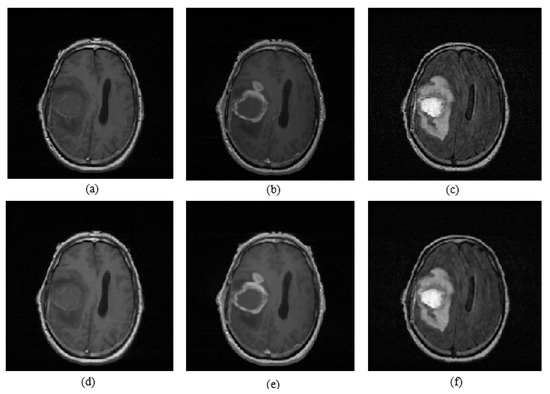

The proposed brain tumor detection and volume estimation algorithm consists of six main stages: median filtering, skull stripping, symmetry analysis, whole tumor segmentation, active core segmentation, and volume estimation. The proposed brain tumor detection and volume estimation algorithm flowchart is given in Figure 1. Initially, noise reduction of the T1, T1C, and FLAIR MR images was realized by median filtering, since an amount of impulsive noises naturally affects MR image slices. The original T1, T1C, and FLAIR MR slices and median filtering results are shown in Figure 2 as an example. Secondly, skull parts of the multimodal brain MR slices were extracted by an adaptive thresholding method. The threshold values were obtained by using histograms of the T1 and T1C images. Third, a symmetry analysis applied on the FLAIR images was performed to detect and label tumor-containing MR slices according to asymmetry scores. Fourth, whole tumor segmentation was realized by using fuzzy c-means (FCM) clustering on the FLAIR MR slices labeled as tumor containing. Fifth, the obtained whole tumor regions were used as the ROI mask for active core detection and segmentation. Active core segmentation relies on the FCM clustering method applied on T1C MRI. Finally, after calculating the areas of the tumor in each MR slice for each patient individually, a volume estimation of the tumor active core was performed by using the calculated areas and also the spacing between slices, and the slice thickness parameters were obtained from the Digital Imaging and Communications in Medicine (DICOM) file.

Figure 2.

(a) T1 image; (b) T1C image; (c) FLAIR image; (d) median-filtered T1 image; (e) median-filtered T1C image; (f) median-filtered FLAIR image.